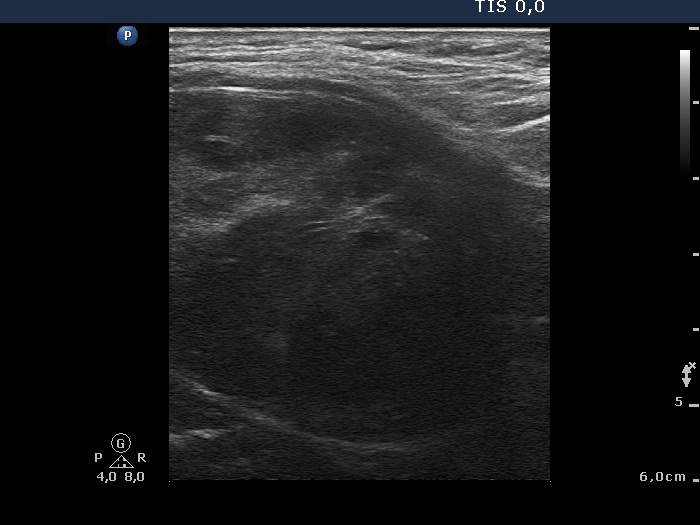

Ultrasonography revealed that the palpable mass contained the enlarged left thyroid composed of a large hypoechogenic nodule with irregular borders and multiple irregular lymph nodes in the left side of the neck.